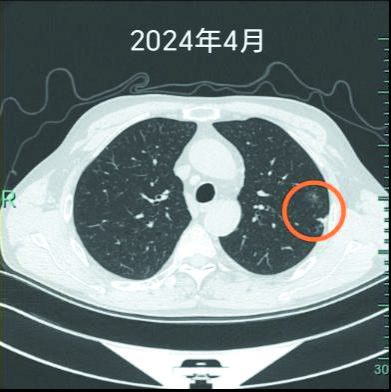

三张图显示,两年间,左上肺的结节越来越明显。

“有些早期肺癌,就像埋在土里的种子。第一颗被我们挖掉了,但可能还藏着另一颗,或者因为长期吸烟造成的‘坏环境’,让新的种子在别处发芽。”心胸外科专家团队用形象的比喻,为杨先生解释了病情。很快又为他实施胸腔镜下左上肺亚肺叶切除术,标本可见明显的胸膜凹陷,剖开可见两枚结节,病理诊断为腺癌。